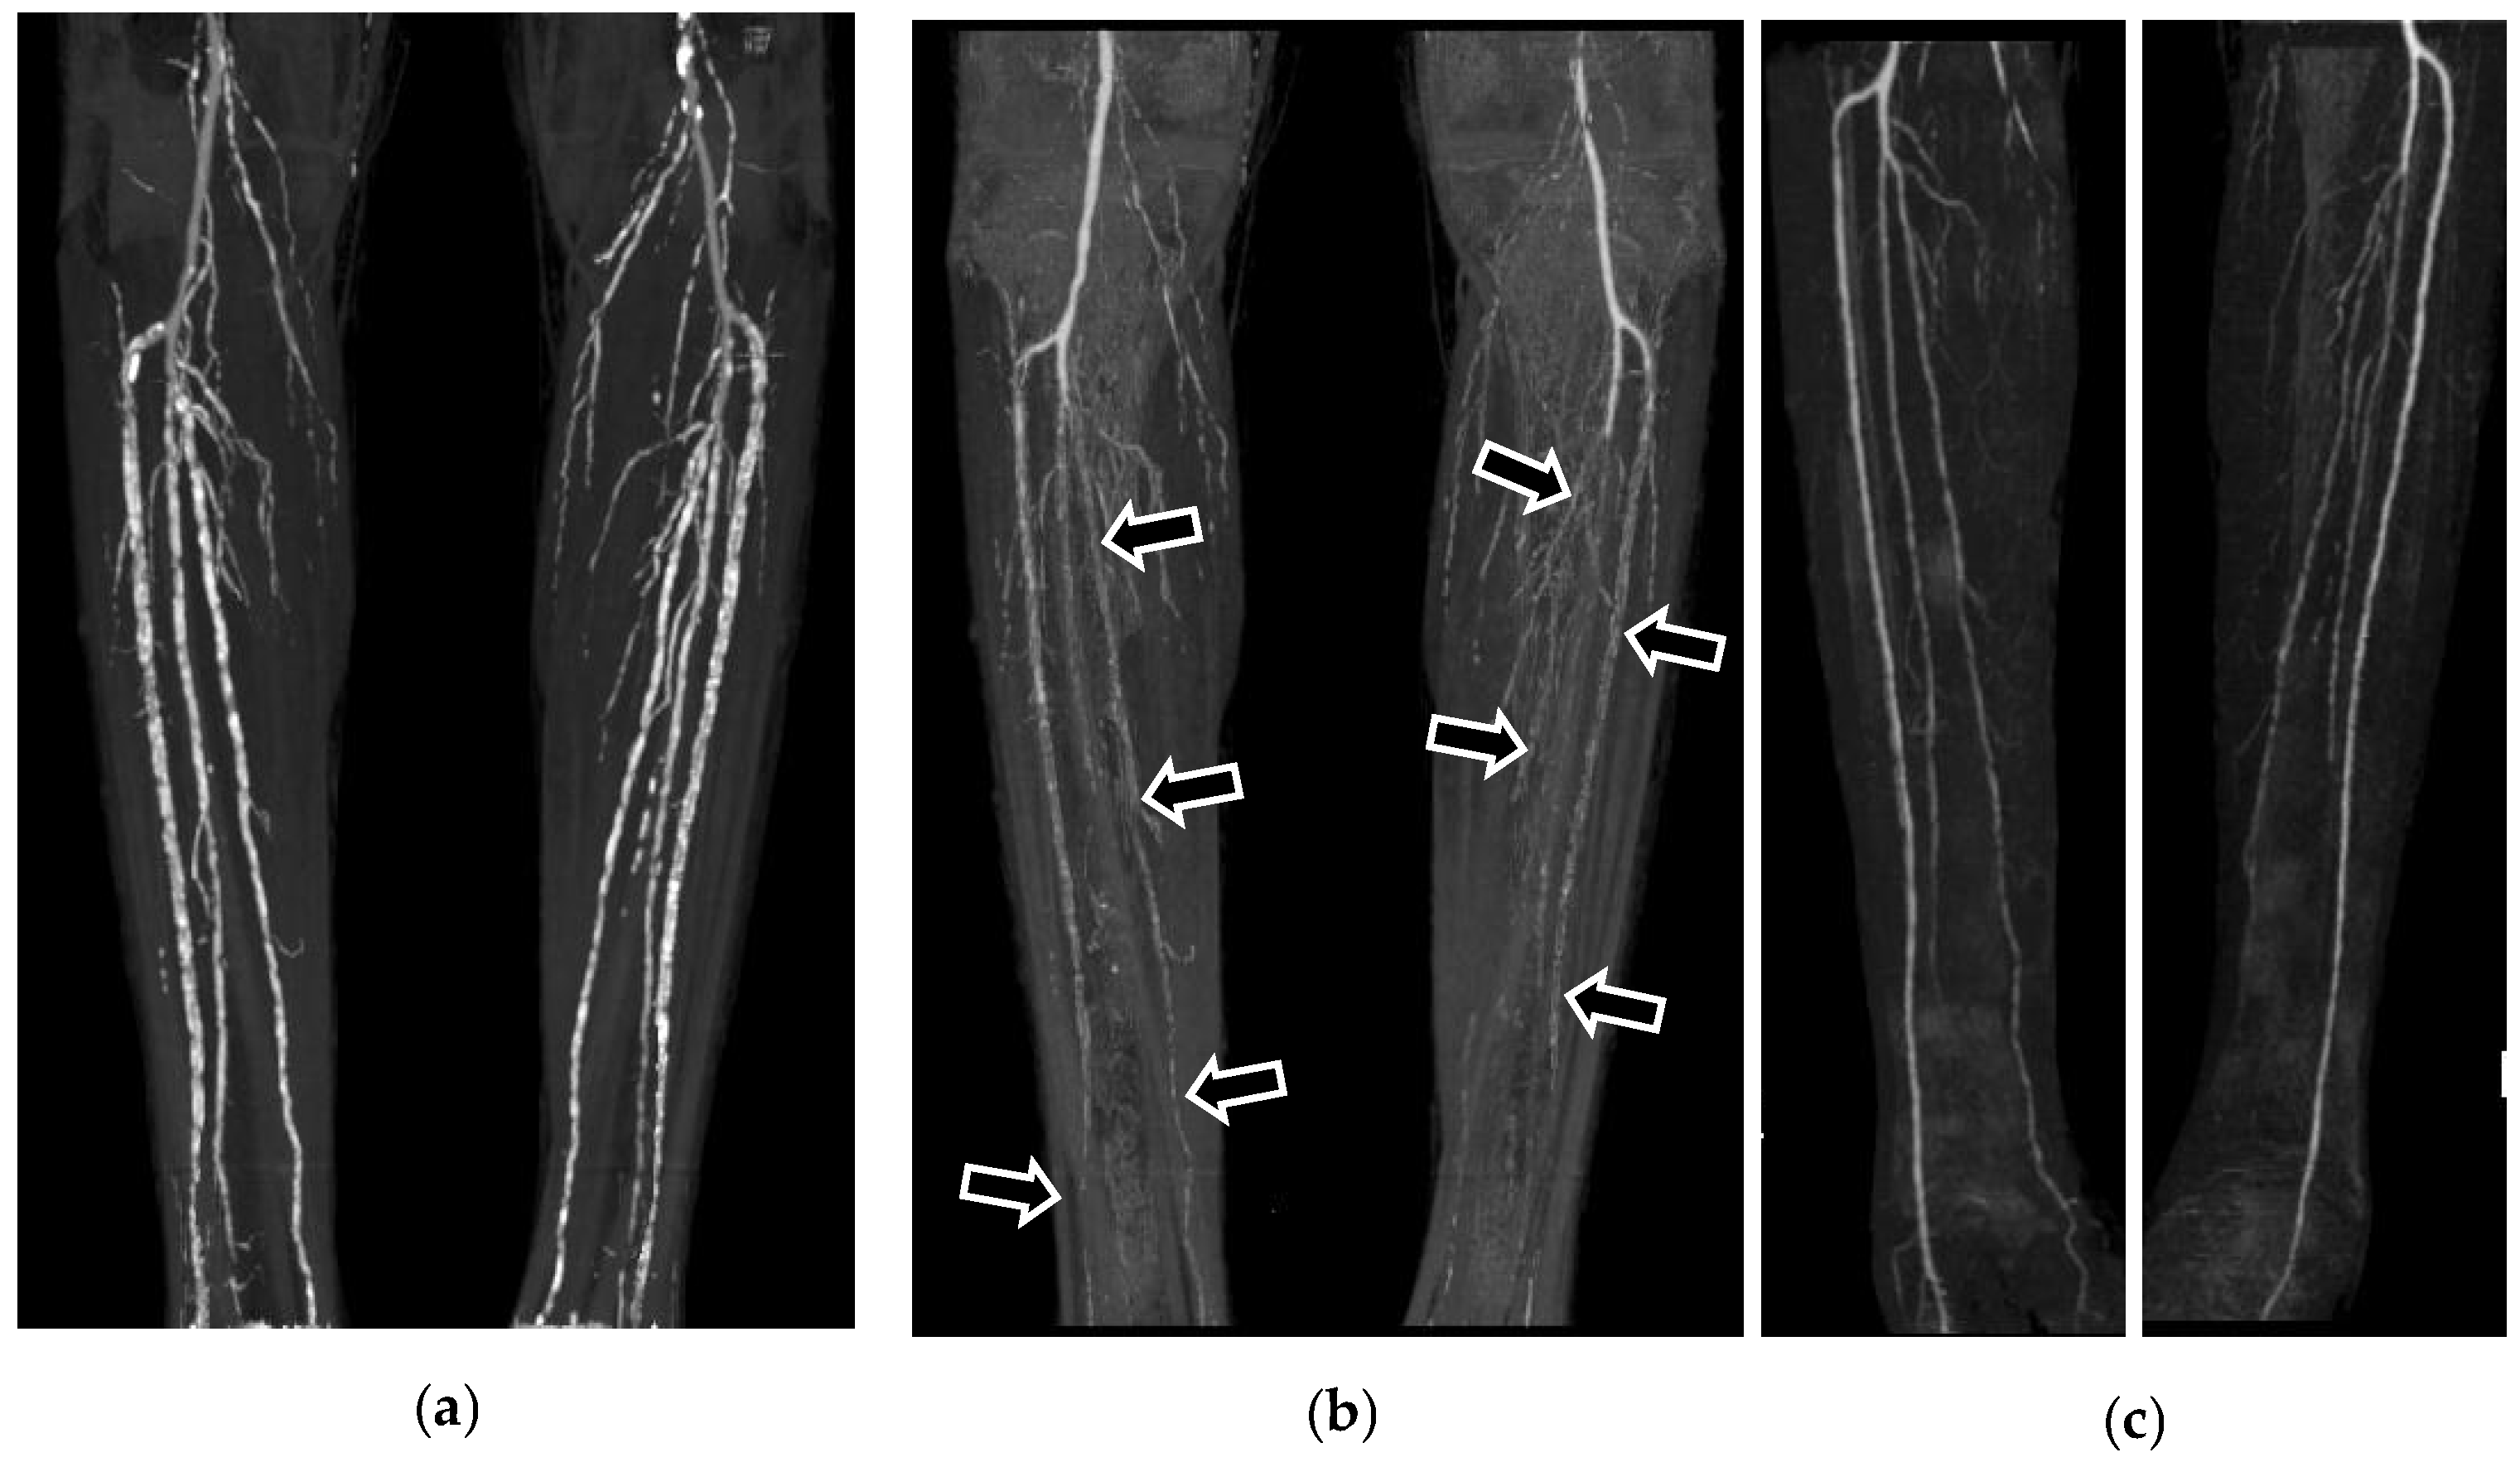

2.2. CT Angiography

3. Results

4. Discussion